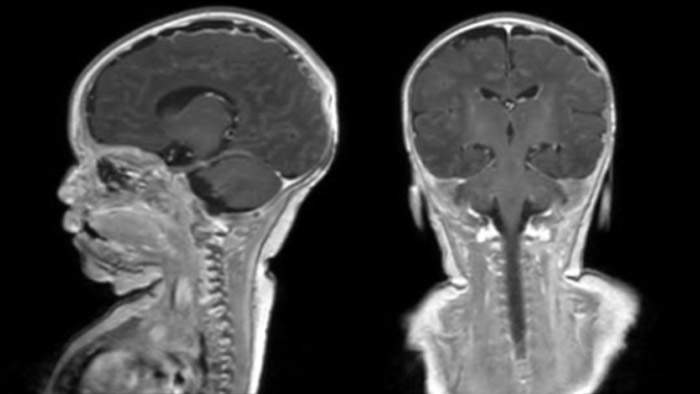

Dural sinus malformation (DSM) Initial examination

After three times of coiling and acryl based embolization

Hydrocephalus post hemorrhagic Both pictures show a ventriculoperitoneal shunt. With our previous scanner our hydrocephalus protocol needed about 25 min. With Ambition the examination time is about 14 min. including a CSF PCA sequence to show flow in the aqueduct.